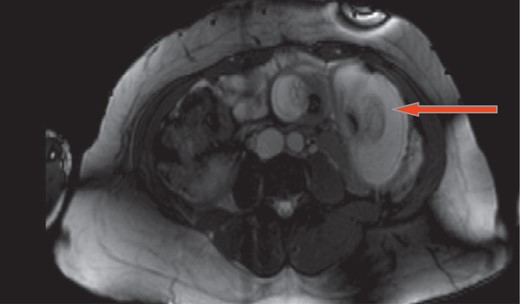

A 37-year-old 6 weeks pregnant female status post-LRYGB 2 years ago presented with 4 hours history of sudden onset of epigastric and peri-umblical pain and tenderness, associated with nausea and vomiting. Vitals signs were stable. Labs including white blood cell count, serum chemistry, urinalysis and liver function tests were all within normal limits. Abdominal ultrasound confirmed intrauterine pregnancy. Magnetic resonance imaging revealed intussusception of small bowel with close loop obstruction (Figs. 1 and 2). Following initial resuscitation, emergent laparoscopy was performed which confirmed the diagnosis. Intra-operatively significantly dilated loop of jejunum approximately 20 cm in length was noticed close to the jejuno-jejunostomy with retrograde telescoping of the jejunum (Fig. 3). At that time decision was made to covert to open laparotomy with resection of irreducible intussusception and reconstruction of jejuno-jejunostomy (Fig. 4). Post-operative course was uneventful, the patient subsequently recovered fully and was discharged home on post-operative day 4. On follow-up, patient was seen in the clinic and reported doing well and pain free. Patient also was following up with her obstetrician to assess the viability of the fetus.

Magnetic resonance imaging shows intussusception of small bowel with close loop obstruction (coronal view).